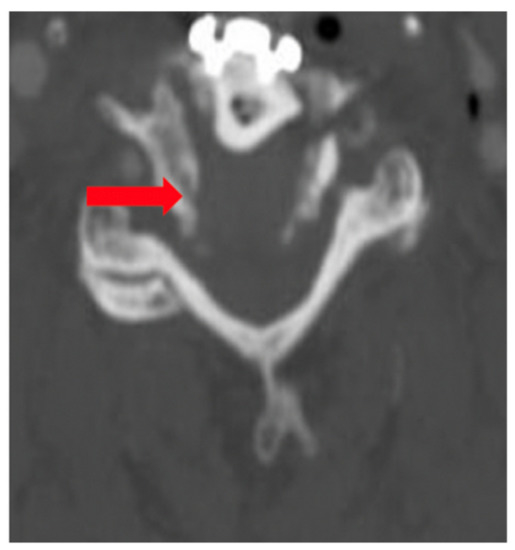

The patient was admitted to the intensive care unit and Mean Arterial Pressures (MAPs) were maintained at 90 mmHg, and he was fully anticoagulated with a heparin drip. He, however, developed significant airway edema and respiratory distress within 24 h after anticoagulation and hypertensive therapy. The patient thus required emergent intubation and subsequent operative hematoma evacuation. Lateral radiograph 1-year post operation shows C4–C7 fusion hardware and resolution of hemodynamic instability (Figure 4).

Figure 4. Lateral Radiograph Post Op 1 Year.